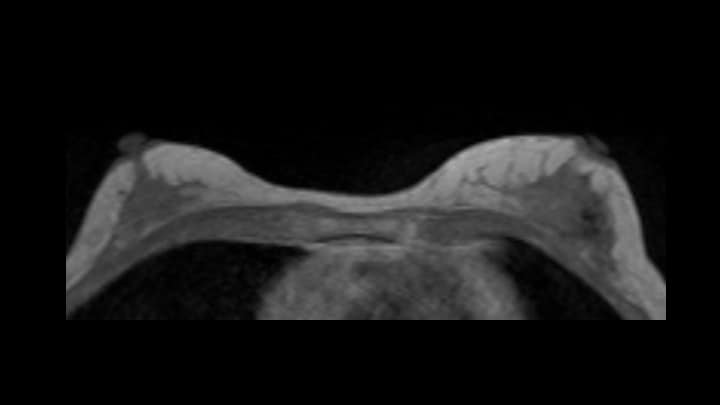

2. T1強調画像(造影前)

4. ダイナミックMRI(造影前)